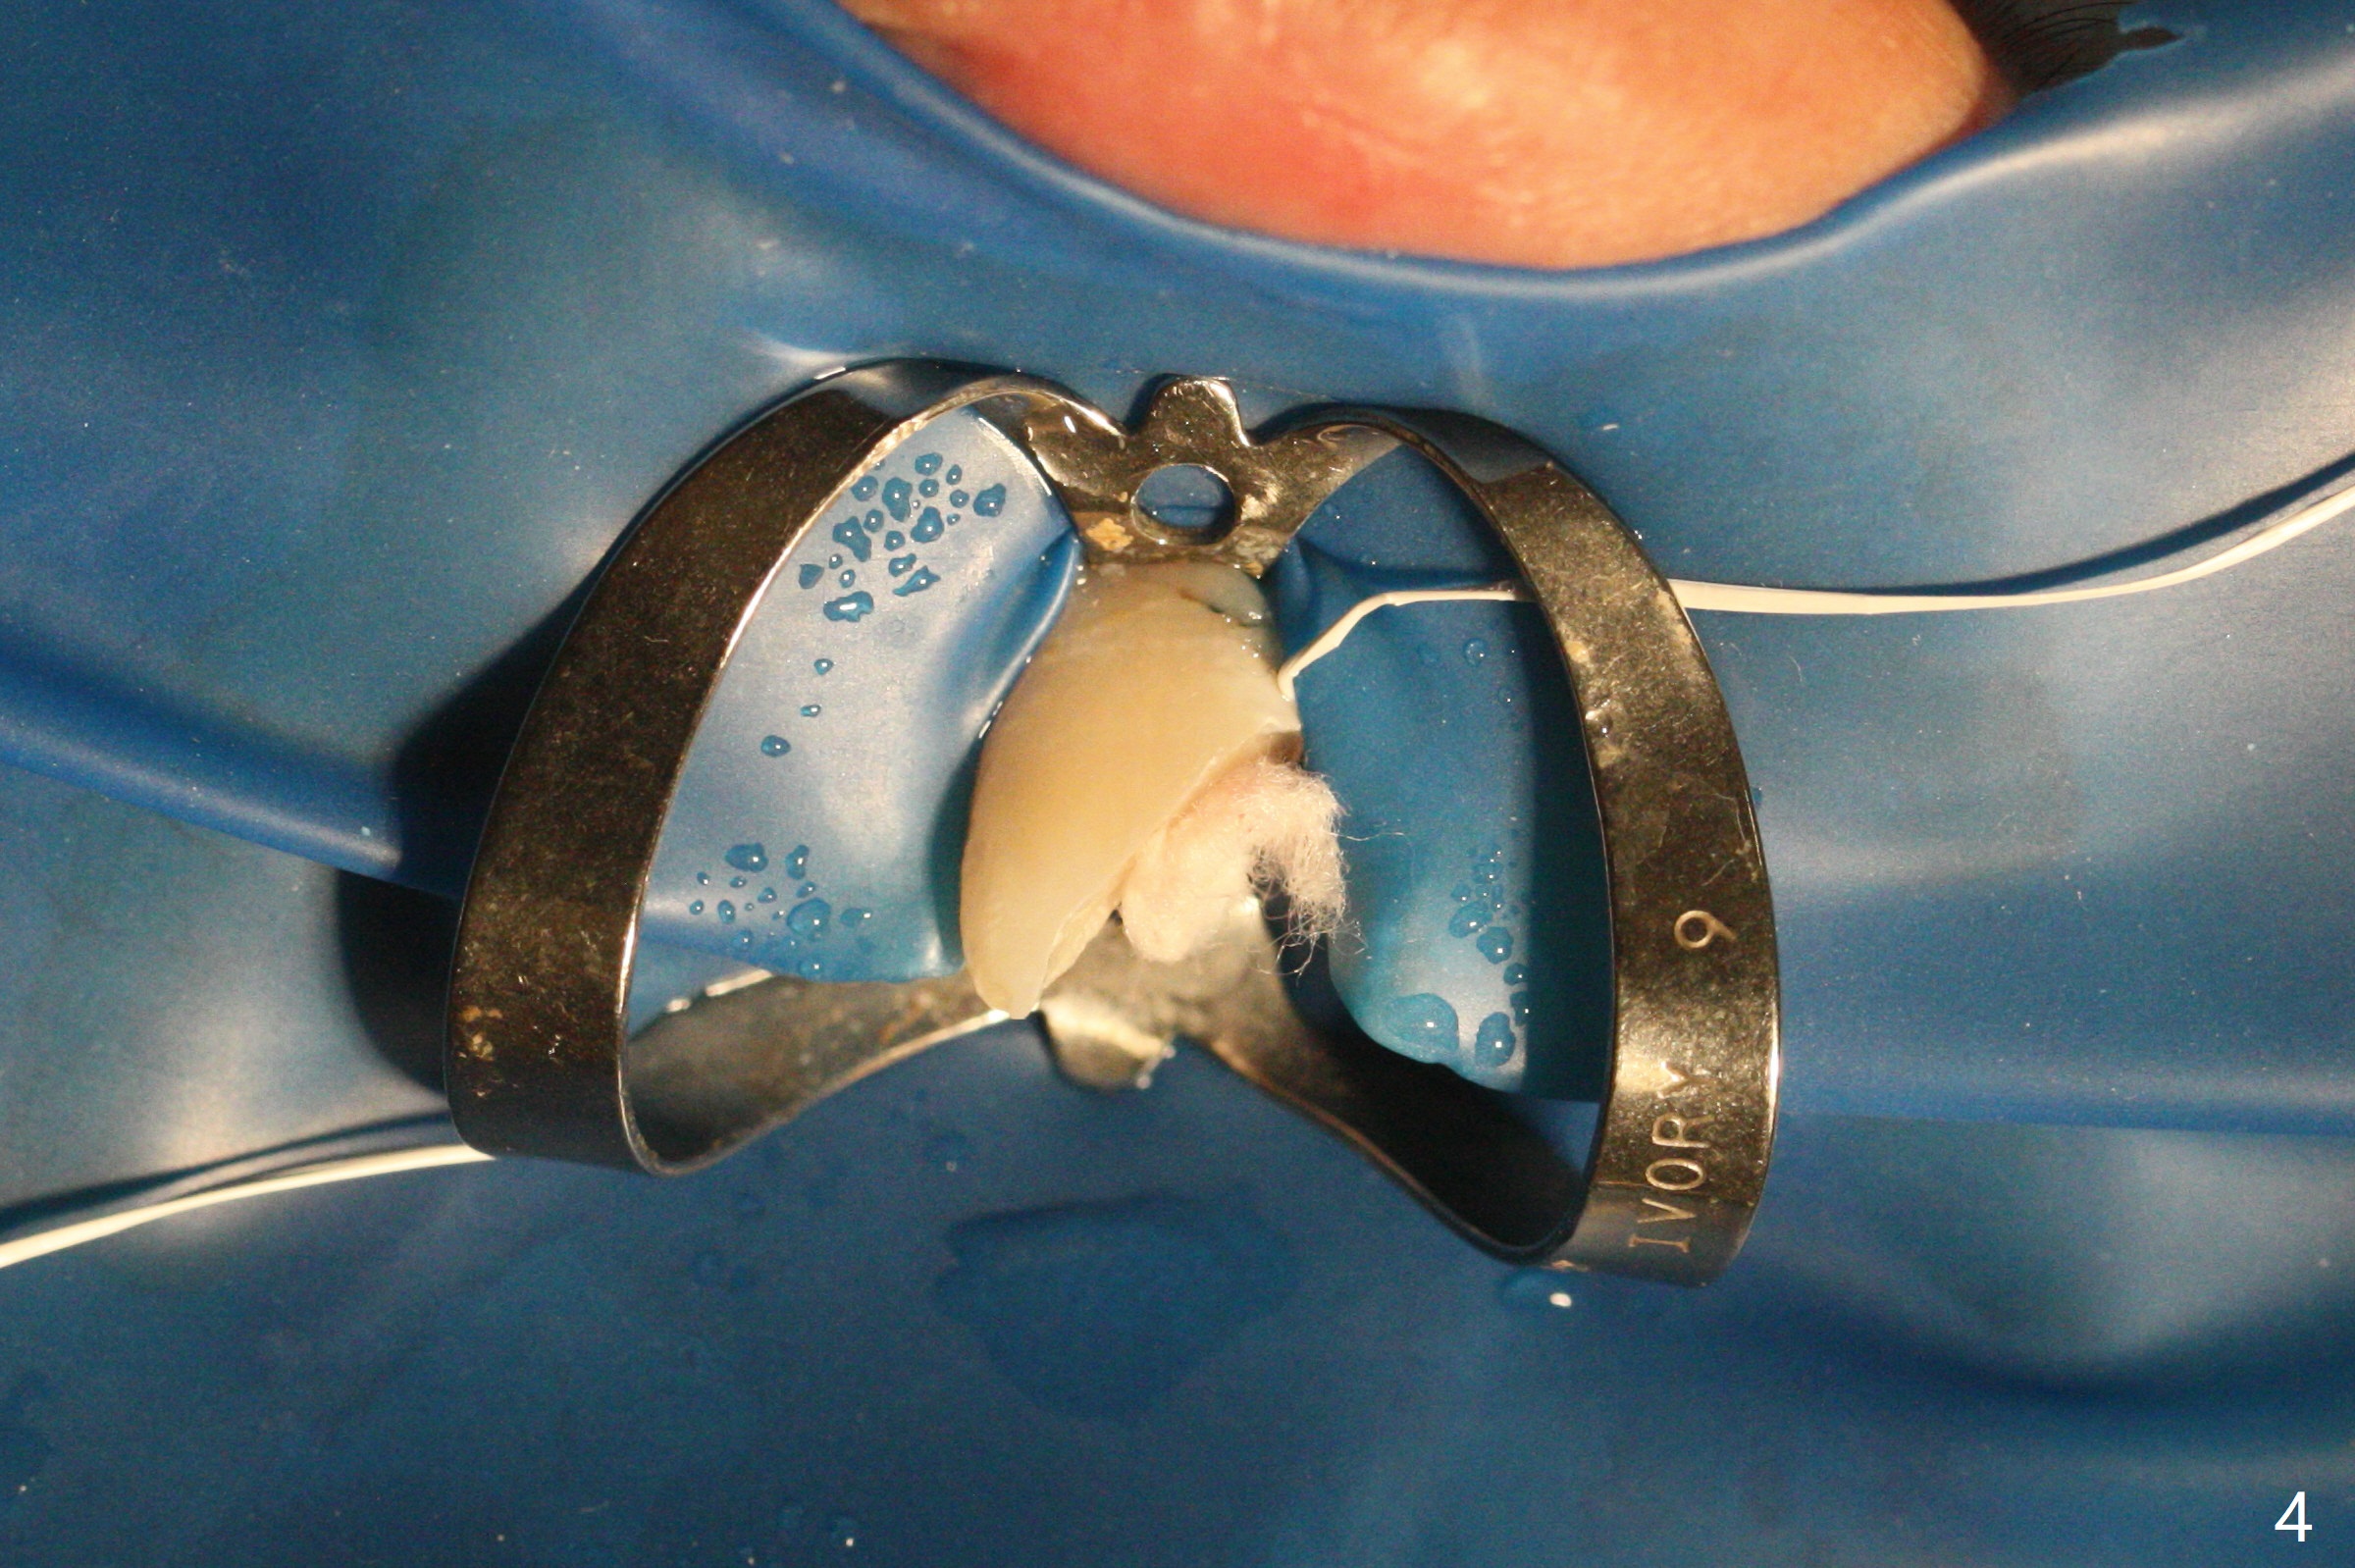

A 16-year-old man fractured the tooth #8 yesterday (Fig.1) with pulpal exposure (Fig.2) and slightly subgingival (Fig.3 <). With 2 gingival retraction cords, rubber dam and floss, the mesial margin is exposed (Fig.4). The mesial pulpal horn is increased slightly with a 330 bur with minimal pulpotomy. MTA is applied (Fig.5 <). A curette is placed over the MTA for hemostasis while it is setting. RelyX Ultimate Adhesive Resin Cement bonding is used to reattach the fracture fragment in place (Fig.6,7). Pulpal vitality will be monitored. A crown will be placed if the tooth discolors due to MTA and the pulp remains vital. Mineral trioxide aggregate (MTA), composed mainly of tricalcic silicate, tricalcic alluminate, bismuth oxide, is a particular endodontic cement. It is made of hydrophilic fine particles that harden in the presence of dampness or blood. The re-attached tooth remains asymptomatic 9 days postop (Fig.8) when he returns for prophy.

16岁男孩,昨天右上中切牙撞击电脑发生折裂(图一),近中牙髓角暴露(图二),裂缘稍微龈下(图三 <),使用两个牙龈牵拉线,橡皮障和牙线,近中折裂边缘暴露(图四)。你会如何处理?使用330钻头稍微扩大髓角开口,去除少量牙髓,填入微量MTA (图五<),希望形成新的牙本质,关闭开口,维持牙髓活性。出血控制后,应用树脂粘合剂将断片固定于原位(图五,六,七)。术后9天牙齿无症状(图八),病人回来洗牙。